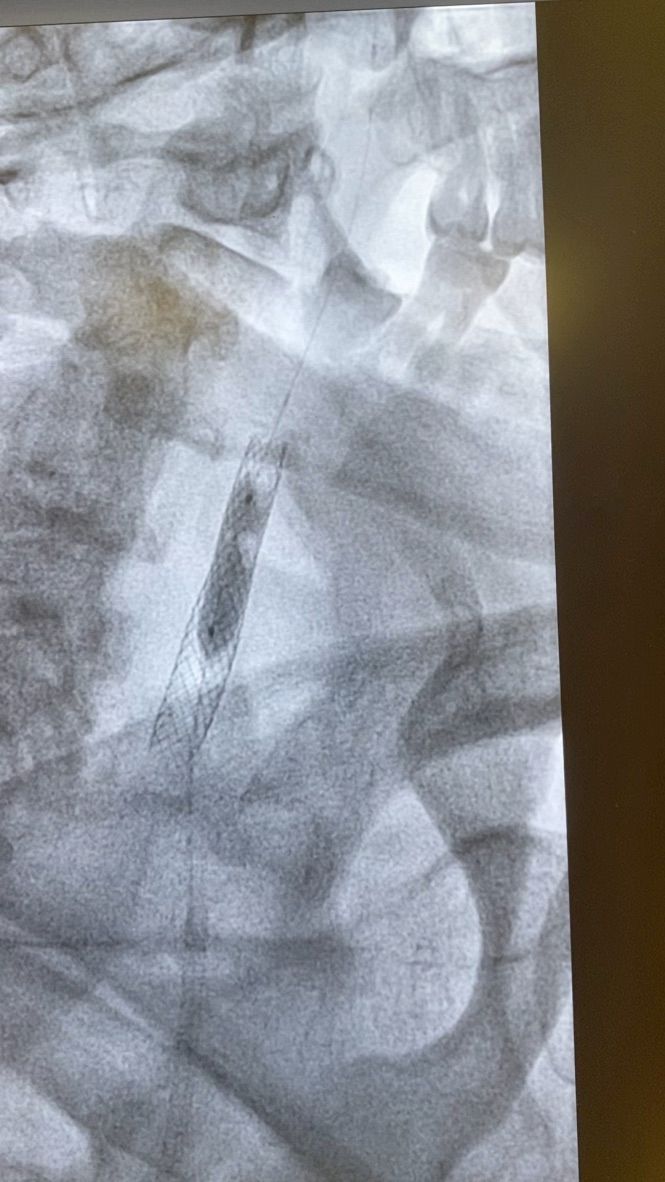

Dal 1997 al 2009 ha lavorato a tempo pieno presso Maria Cecilia Hospital di Cotignola come Cardiologo interventista eseguendo procedure interventistiche di PTCA sul distretto coronarico, carotideo, PTA del distretto iliaco-femorale, renale, e tibiale; Procedure percutanee di impianto di endoprotesi nel in aorta toracica e addominale, impianto percutaneo di valvole aortiche (TAVI), chiusura di Difetti interatriali e forami ovali.

VALUTAZIONE DI PROCEDURE INTERVENTISTICHE (vascolare, patologie delle carotidi, delle arterie iliacofemorali, arterie tibiali nel piede diabetico, aorta addominale e toracica) E CARDIOLOGICHE (angioplastiche coronariche, TAVI, chiusura di difetti interatriali e forami ovali pervi)